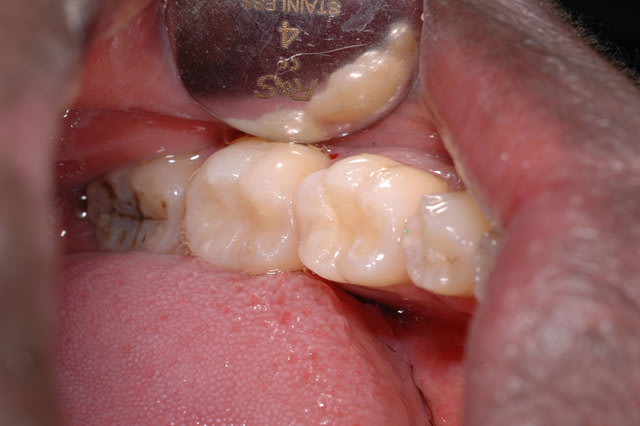

en oubliant black et ses extensions préventives ...

Oui c'est mieux mais pourquoi ne pas avoir touché à la 8?